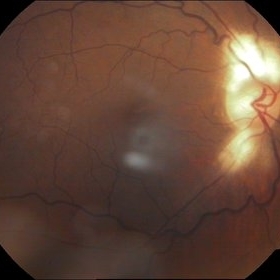

Myopic Degeneration, Macular Hemorrhage

Sep 10 2014 by Mehul A Shah

A 50-year-old male patient presented with complaint of sudden loss of vision.

Photographer: Drashti Netralaya,Dahod

Imaging device: FF 450

Condition/keywords: myopic degeneration